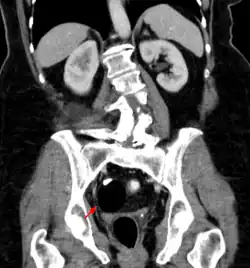

Les tératomes de l'ovaire

Les tératomes immatures de l’ovaire, souvent détectés à l'échographie, TDM ou IRM[21] sont potentiellement malins tout comme les tératomes testiculaires, qui sont généralement moins bien différenciés (donc avec un pronostic plus sombre). Des effets hormonaux, systémiques ou éloignés (ex. : encéphalite limbique paranéoplasique, encéphalite paranéoplasique anti-NMDAr)[22] sont possibles. Les métastases sont rares mais possibles (ex. : métastases neuroïdes matures d’un tératome ovarien[23]). Après ablation, des récidives sont possibles[24].